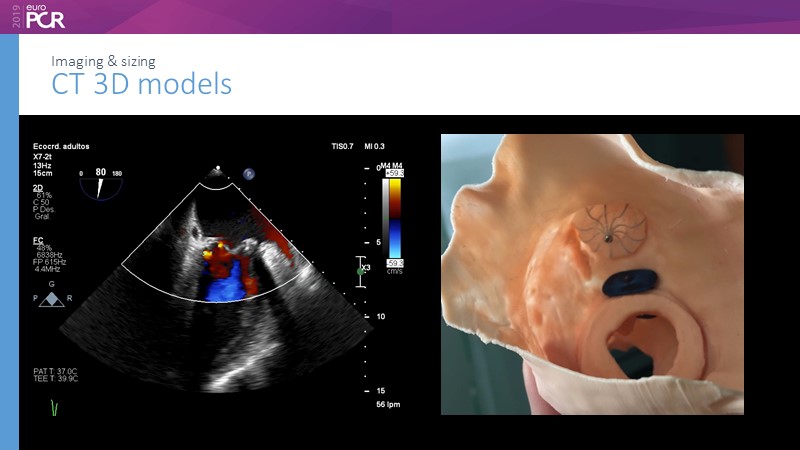

Pre-procedure planning

Previous Next